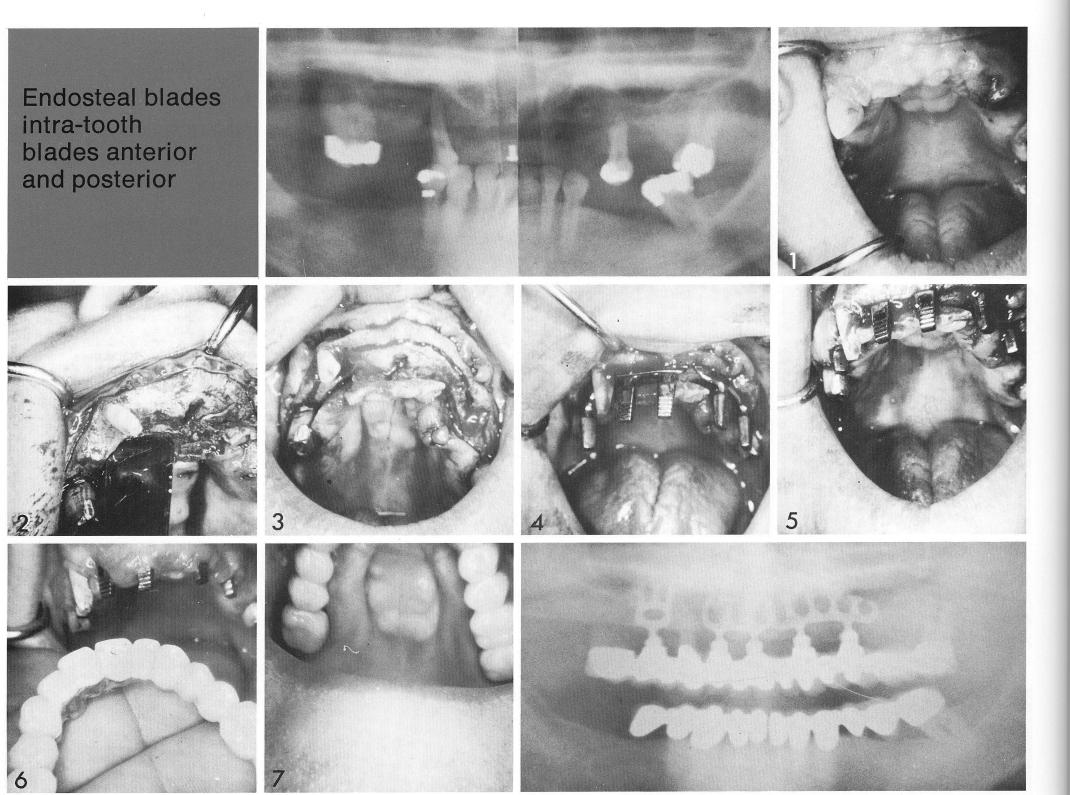

Endosteal blades

intra-tooth blades anterior and posterior

The prominent torus illustrates one of the most therapeutically satisfying solutions permitted by the use of implants. The partially edentulous patient (1) had an unusually wide ridge (2), but a narrow arch. As many anterior abutments as possible were desirable. The extreme width of the ridge permitted crossing the midline (3) with a bladevent socket without threatening the anterior palatine foramen. The bladevents were inserted (4,5), and shortly thereafter the final restoration. The advantage of a palateless restoration is clearly obvious (6).

1 Partially edentulous patient with unusually wide maxillary ridge